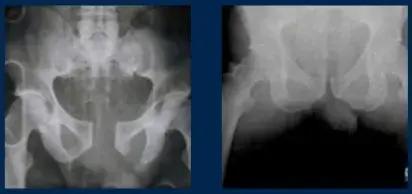

X-rays before and after using T-Pod®